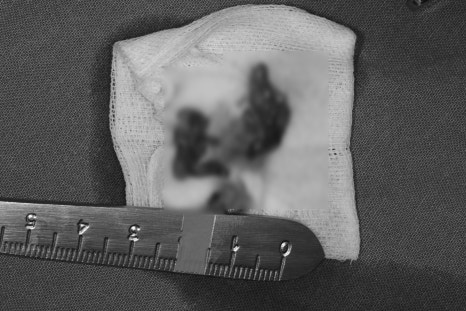

③ Complete removal and curettage of the lesion – complete removal of the bony tumor tissue, including the lesion capsule

⑤ Pathology request (biopsy) – the removed lesion was sent to a pathologist for final diagnosis

✅ Diagnosis

Oral cavity, mandible, posterior, Rt., excision:

Consistent with periapical cyst, ruptured, with abscess formation.

→ It is presumed to be a periapical cyst, and it has ruptured with abscess formation. It was confirmed that a cyst that had formed at the end of the tooth root ruptured, leading to pus formation. If a cyst becomes larger or inflammation persists for a long time,

rupture and infection may occur.

📌 Interpretation: The lesion is judged to be an inflammatory periapical cyst,

which is a representative cyst that usually forms at the root tip of a tooth due to dental infection or trauma.